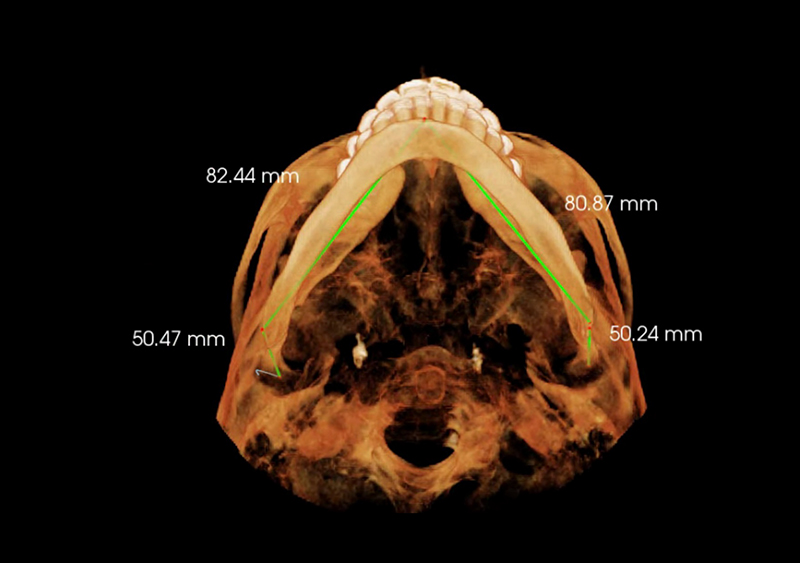

Estudio de Simetría

Nos permite analizar las distintas estructuras craneofaciales y su

relación entre si, para determinar biotipos faciales y predecir líneas de

crecimiento y desarrollo, además de posibles compensaciones